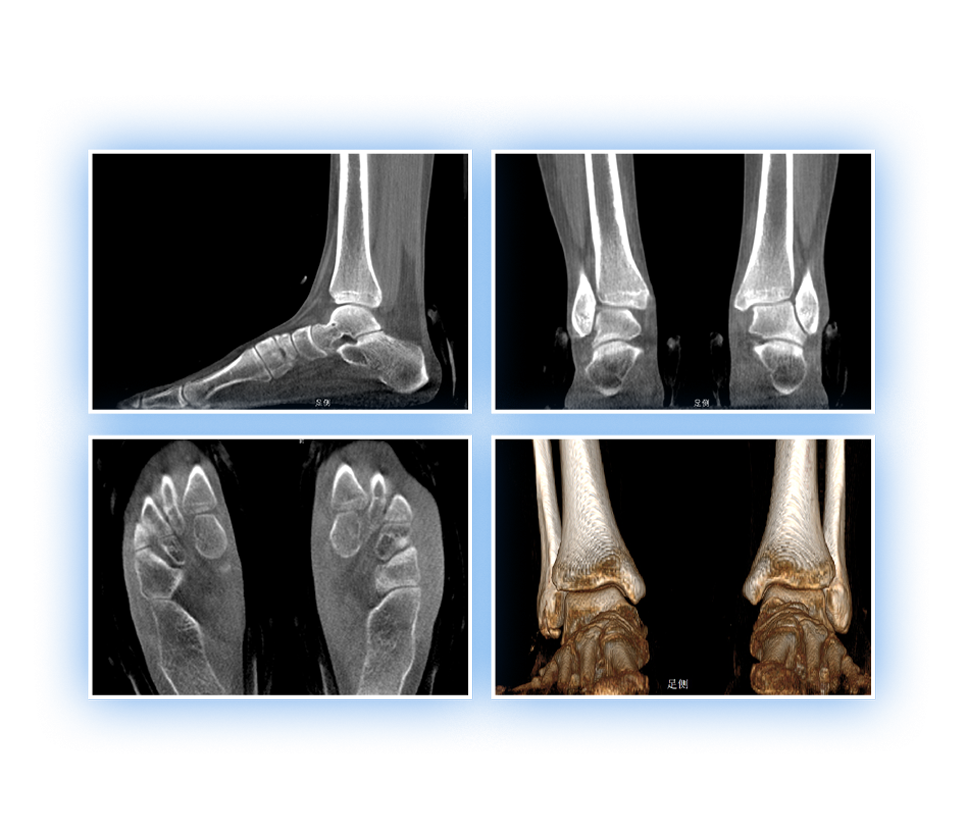

髋关节

精准诊断

手术方案规划

术后随访